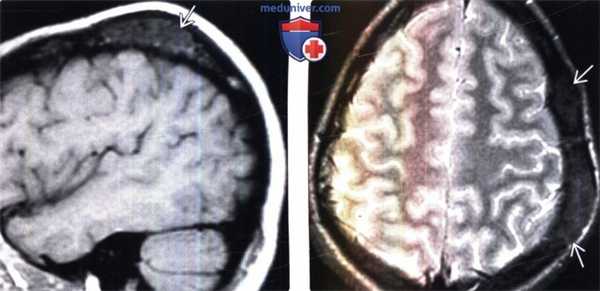

(Слева) МРТ, Т1 -ВИ, сагиттальный срез: у юноши 77 лет с медленно увеличивающейся в размерах «шишкой на волосистой части головы» определяется объемное образование свода черепа, которое имеет умеренно гипоинтенсивный сигнал.

(Справа) МРТ, Т2-ВИ, режим подавления сигнала от жира, аксиальный срез: у этого же пациента отмечается, что поражение имеет слегка неоднородный гипоинтенсивный сигнал.